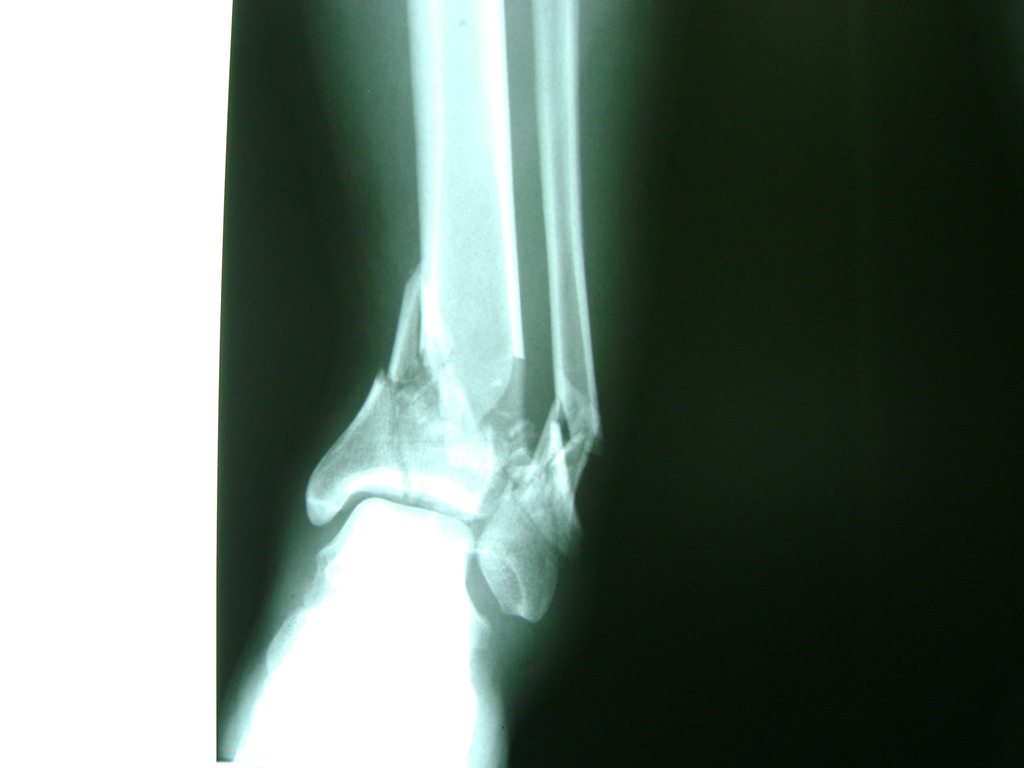

Una fractura de tobillo es la rotura de uno o más de los huesos del tobillo. Estas fracturas pueden ser:

- Parciales (el hueso está sólo parcialmente fisurado, no del todo).

- Completas (el hueso está perforado y está en 2 partes).

Algunas fracturas de tobillo pueden requerir cirugía si:

- La fractura se extiende hasta la articulación del tobillo (fractura intra-articular).